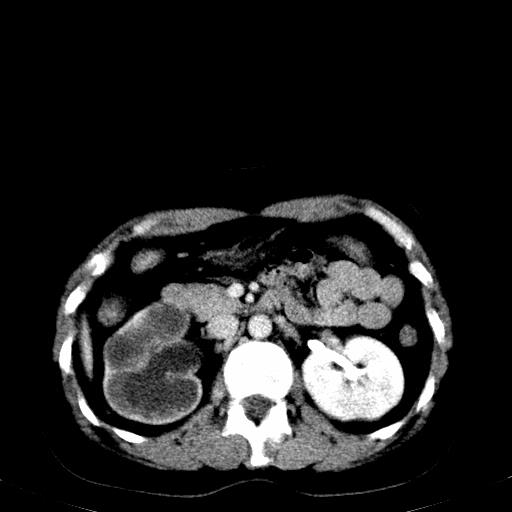

患者体检发现右肾体积增大,怀疑右肾积水

右肾重度积水,以肾盏积水明显,有分隔,上段输尿管轻度扩张,管壁增厚,考虑肾结核可能,请结合尿检查,胸部拍片排除肺结核。

右肾重度积水,建议ct向下扫描或逆行造影,左肾及左输尿管结石 .

1)不排除右肾结核可能。2)左肾及左输尿管上段结石?

左肾不是结石,是造影后改变.右肾积水,功能仅存.